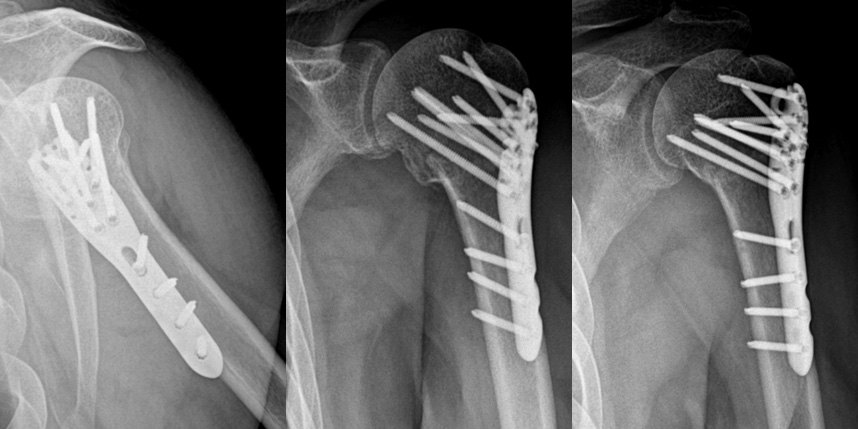

상완골 골절